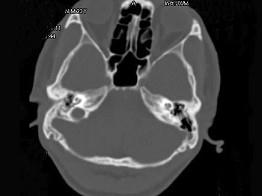

问题 男,23岁,右耳流脓十余年,右外耳道流脓,鼓膜穿孔,CT检查如图,最可能诊断为 ( )

选项 A、嗜酸性肉芽肿 B、(海绵化期)耳硬化症 C、中耳乳突结核 D、中耳癌 E、慢性中耳乳突炎

答案 E